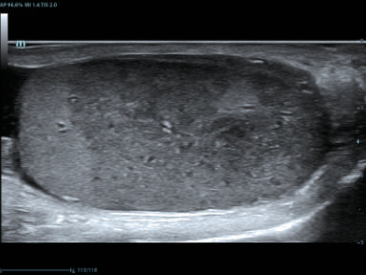

–Θ–Μ―¨―²―Ä–Α–Μ–Β–≥–Κ–Η–Ι –Ψ–±―ä–Β–Φ–Ϋ―΄–Ι –¥–Α―²―΅–Η–Κ ―¹ –≤―΄―¹–Ψ–Κ–Ψ–Ι –Ω―Ä–Ψ–Η–Ζ–≤–Ψ–¥–Η―²–Β–Μ―¨–Ϋ–Ψ―¹―²―¨―é

–Θ–Μ―¨―²―Ä–Α–Μ–Β–≥–Κ–Η–Ι –Η –≤―΄―¹–Ψ–Κ–Ψ–Ω–Μ–Ψ―²–Ϋ―΄–Ι –Ψ–±―ä–Β–Φ–Ϋ―΄–Ι –¥–Α―²―΅–Η–Κ –Ψ–±–Β―¹–Ω–Β―΅–Η–≤–Α–Β―² –Ω―Ä–Β–≤–Ψ―¹―Ö–Ψ–¥–Ϋ–Ψ–Β –Κ–Α―΅–Β―¹―²–≤–Ψ –≤–Η–Ζ―É–Α–Μ–Η–Ζ–Α―Ü–Η–Η –≤ –Α–Κ―É―à–Β―Ä―¹―²–≤–Β –≤ ―Ä–Β–Ε–Η–Φ–Α―Ö 2D, –Π–î–ö, 3D/4D –¥–Μ―è –±–Ψ–Μ―¨―à–Β–Ι –¥–Η–Α–≥–Ϋ–Ψ―¹―²–Η―΅–Β―¹–Κ–Ψ–Ι ―É–≤–Β―Ä–Β–Ϋ–Ϋ–Ψ―¹―²–Η –Η –Ω–Ψ–≤―΄―à–Β–Ϋ–Η―è –Κ–Α―΅–Β―¹―²–≤–Α –Η―¹―¹–Μ–Β–¥–Ψ–≤–Α–Ϋ–Η―è;